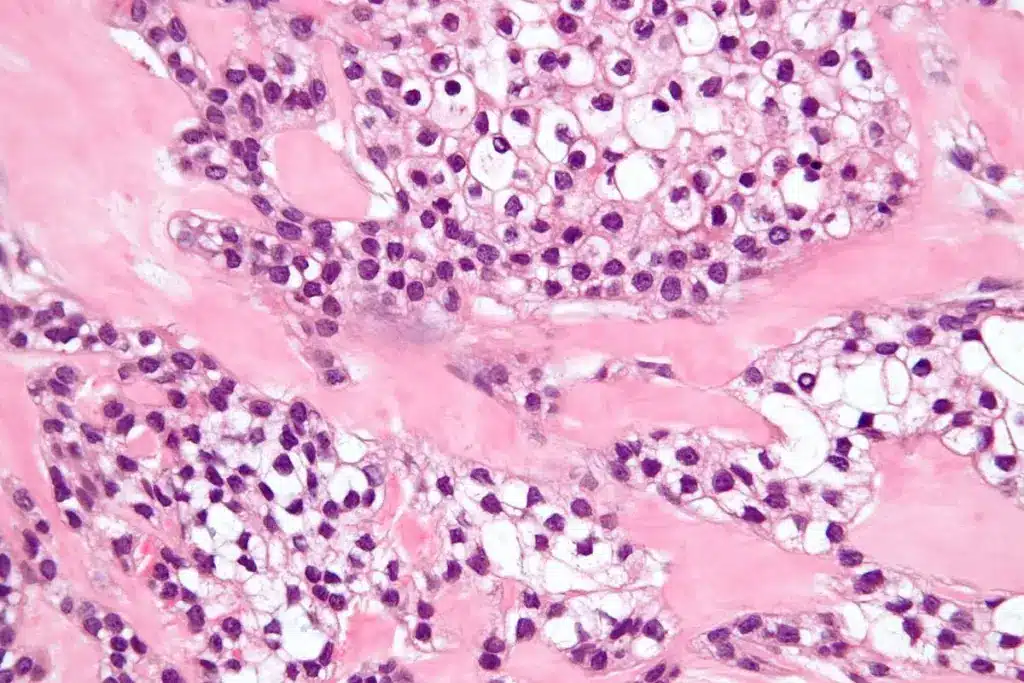

Histopathological Examination

This step looks at tissue under a microscope for abnormal growth. It helps doctors figure out the cancer type and grade. This is vital for treatment planning.

A biopsy takes a tissue sample for lab tests. It might use numbing or sedation to make you comfortable. Then, the sample is checked for cancer cells under a microscope.